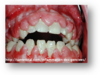

DIABÈTE ET GENCIVES :

Le diabète diminue les défenses immunitaires et retarde la cicatrisation. Il dérègle le mécanisme de l’inflammation, dérègle celui de la réparation osseuse et gingivale. Autre répercussion particulièrement perverse : à cause de la modification du seuil de la douleur, les affections dentaires restent plus longtemps silencieuses, le patient ne consulte pas et son état empire à son insu.

Ainsi toute attaque microbienne de la gencive et des mâchoires aura des conséquences parfois catastrophiques sur les dents, qui, à terme, pourront tomber spontanément (par déchaussement).